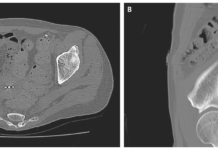

A 74-year-old woman presented to the gastroenterology clinic with complaints of abdominal distention and bloating.

Physical examination showed a distended abdomen. However, the abdomen was non-tender on palpation with normal bowel sounds. An esophagogastroduodenoscopy was performed which showed numerous mucosal masses in the duodenum with pillow sign (subepithelial lesion indenting when prodding with biopsy forceps). The subepithelial lesion was biopsied and unroofing of the biopsy revealed yellow adipose tissue. Histopathological analysis showed mature adipose tissue.

The findings were consistent with the diagnosis of intestinal lipomatosis.